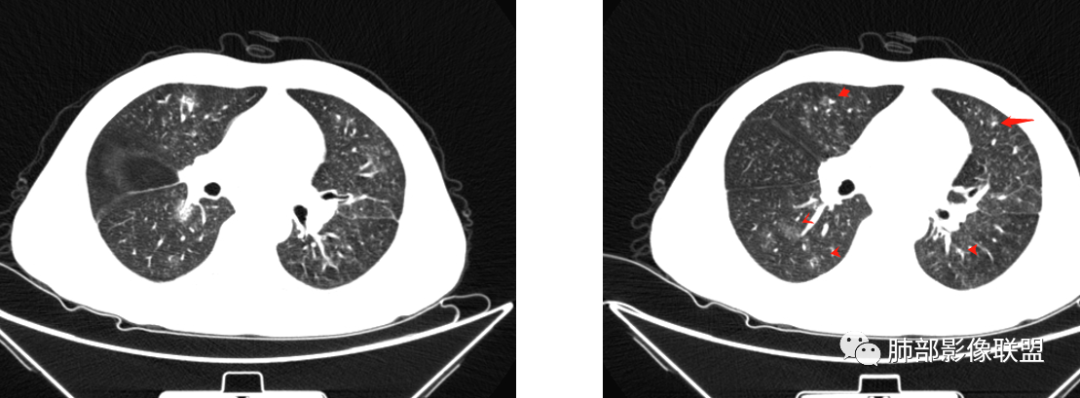

晨读:双肺不均匀分布片状,斑片状影,边缘有晕,部分病灶内见支气管像,密度不均。50多天3次CT复查,病变此起彼伏。考虑病毒>OP>吸入。

晨读:双肺不均匀分布片状,斑片状影,边缘有晕,部分病灶内见支气管征,密度不均。常规考虑OP,但是结核病人肝肾功能,还是考虑真菌,隐球菌可能,其次结核待排。

病史,中年男性,乏力纳差,高血压,肾功能不全,贫血。影像,双肺多结节,斑片影,后期吸收,考虑肺水肿?血管炎?

病灶此起彼伏,肾功异常,部分病灶有晕,考虑肉芽肿性多血管炎。

双肺多发实变及磨玻璃影,边界欠清,部分可见小叶间隔增厚,支气管穿行病灶内,多次随访复查,部分有吸收又似有新发,双侧纵隔淋巴结肿大,临床:男性49岁,肾功能异常,考虑GPA,OP

患者,男,49岁,初次以头晕呕吐肾功能异常入院,后期伴双下肢水肿,CT示双肺多发斑片及结节影,部分周围伴晕,部分内部可见支气管穿行,多次复查可见部分病灶略吸收及新发病灶出现,最后一次复查双肺多发磨玻璃样改变,综合考虑血管炎,最后一次伴肺水肿可能

中年男性,高血压,肾功能衰竭,贫血病史,尿潜血阳性。3.8双肺野多发斑片磨玻璃实变影,结节影,边缘模糊,周围有晕征,内见支气管充气征,主要沿支气管血管束分布,部分胸膜下分布,3.12号病灶有吸收好转,4.8号斑片实变影基本吸收,主要沿支气管血管束分布结节影,边缘平直收缩,4.28病灶大部分吸收好转,双肺支气管血管束增粗,有少量结节影。考虑ANCA相关性血管炎可能性大,第一次片子觉得隐球菌不排除,但是后面没有抗真菌治疗就吸收了,觉得隐球菌可能性不大。

两肺多发团片状高密度影

南边:

边界模糊,距离胸膜有间隙,内部支气管通畅